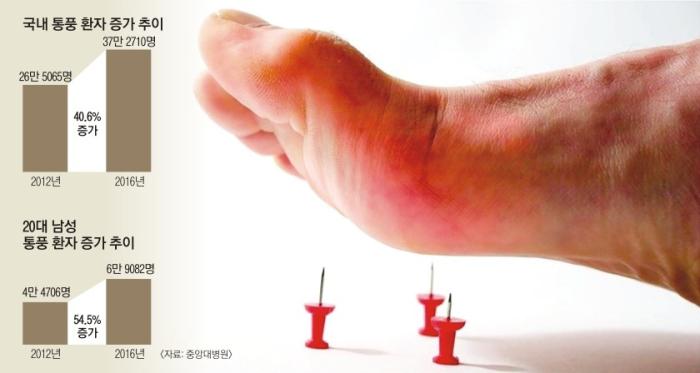

통풍 환자는 거의 남자이고 대개 첫 발작적 관절염을 40~50세에서 경험합니다.

한때 통풍은 좋은 음식을 먹고 술 마시는 부유층의 병으로 간주되기도 했지만

요즘은 식생활이 윤택해지면서 사회계층에 관계없이 발생합니다.